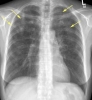

У большинства больных легочный эозинофильный инфильтрат, связанный с аскаридозом и другими глистными инвазиями, протекает бессимптомно и выявляется при профилактических флюорографических исследованиях. Температура тела, как правило, нормальная, иногда она повышается до суб- фебрнльных цифр с нормализацией в течение нескольких дней. У некоторых больных появление легочного эозинофильного инфильтрата сопровождается недомоганием, головной болью, ночными потами, кашлем без мокроты или с незначительным количеством окрашенной в желтый цвет мокроты.

Клиническая картина легочного эозинофильного инфильтрата, возникающего после применения фурадонина, описана особенно подробно. Реакции легких на прием фурадонина бывают острыми и хроническими. При остром варианте реакции через 2 ч-10 дней после начала приема фурадонина появлялись лихорадка, сухой кашель, насморк, одышка. На рентгенограммах обычно выявляются диффузные изменения в легких, иногда очаговые неправильной формы инфильтраты в легких, отсутствовали типичные для синдрома Леффлера быстрое исчезновение и миграция инфильтратов, иногда появляется выпотной плеврит, причем в плевральной жидкости содержится много эозинофилов. Характерно увеличенное содержание эозинофилов в крови. При остром течении заболевания вскоре после отмены препарата исчезает эозинофильный инфильтрат в легком. При хроническом течении заболевания рассасывание легочного эозинофильного инфильтрата затягивается, и в отдельных случаях на его месте развивается пневмосклероз.